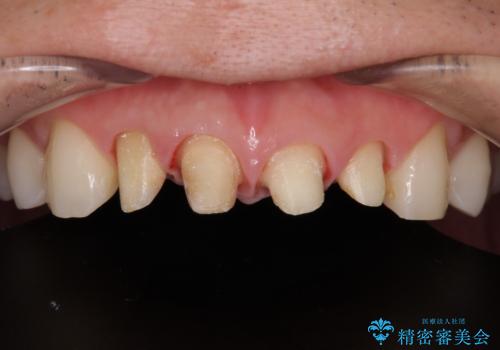

- 以前他院で治療を行った前歯の被せものが欠けてしまい、きれいなセラミックにしたいと来院された患者様です。

人工物のような印象が強くあまり自然とは言えない状態でした。

また被せものと土台の間に隙間があり、適合もよくない状態でした。